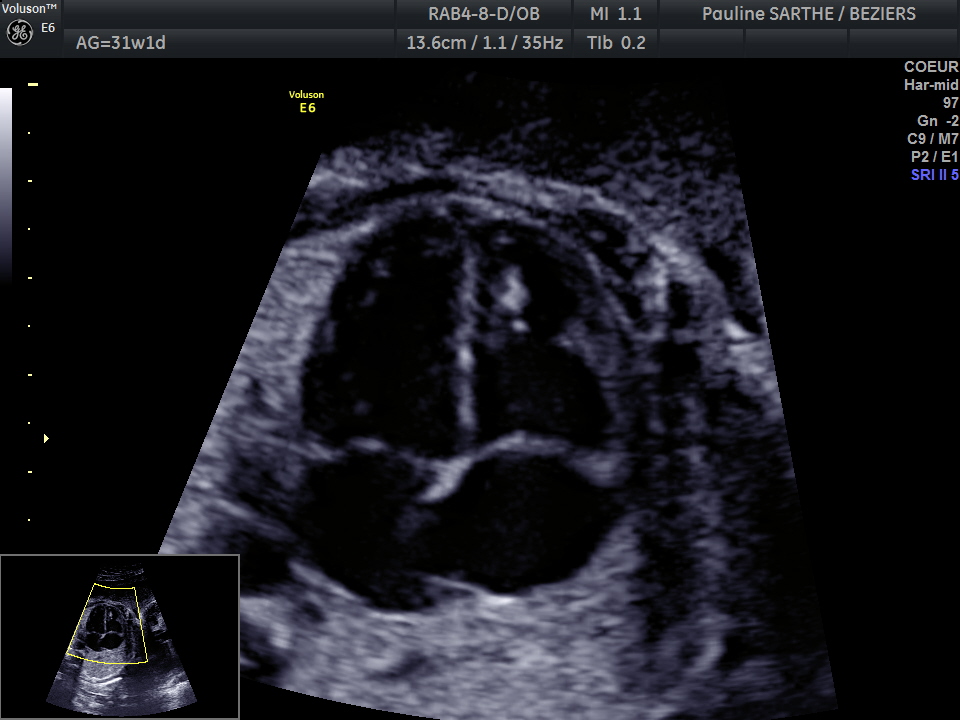

- l'échographie du 3 ème trimestre s'effectue de manière optimale entre 32 et 34 semaines d'aménorrhées.

Elle est importante pour s'assurer de la bonne croissance, de l'aspect des organes, de la position de votre bébé et du placenta à l'entrée dans le dernier trimestre.